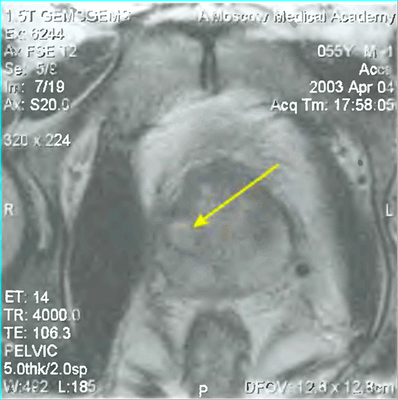

МРТ: рак простаты Т2а и Т3а (стрелки указывают на вовлеченность капсулы в опухолевый процесс)

А - магнитно-резонансная томограмма демонстрирует неровность контура капсулы левой доли простаты с распространением мягкотканного компонента за ее пределы (стрелка), Т2 ВИ. В - изображение после динамического введения гадолиния. С - после обработки компьютерной программой - явное усиление интенсивности МР-сигнала в зоне патологии, типичное для неопластического перерождения

Рак левой доли предстательной железы с разрушением капсулы и ростом в перипростатическую клетчатку